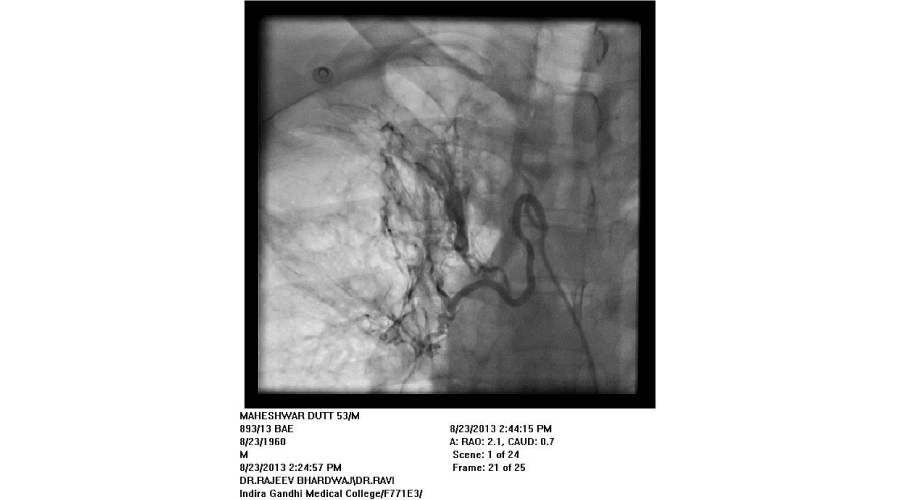

Patients admitted with moderate to severe hemoptysis in pulmonary medicine or general medicine department were the subjects of study. The patients were subjected to routine blood examination, X ray of chest, and CT scan of chest (Except in emergent situation). If required, bronchoscopy was done to localize the side of bleeding and for diagnostic purposes. Informed consent was taken from all patients. Commonest approach was from right femoral artery puncture. Seven French sheath was inserted in the femoral artery with the help of Seldienger technique. According to the protocol, bronchial arteries, intercostal arteries, subclavial arteries and its branches including the internal mammary arteries were selectively hooked with a catheter and contrast was injected into these arteries to see for the signs of bleeding. Initial attempt was made to see for bleeding source on the side suggested by X-ray or CT scan or bronchoscopy. Before the completion of procedure, vessels of other side were screened. If no bleeding vessel was found after screening on both sides, pulmonary arteriography was done with pig tail catheter to see for the source of bleeding from pulmonary artery. An artery was considered abnormal/ potential bleeder, if extravasation of contrast, aneurysm, increased caliber with tortuosity, vascular tufts, arterio-arterial or arterio-venous fistulas were seen. Once diseased artery was identified, it was selectively cannulated with a catheter. Most commonly used catheters were right Judikin, Cobra I, and Simmon I. The vessels were hooked deeply with the catheter, with the support of .018 inch guide wire. The vessel was then embolized with poly vinyl alcohol (PVA) particles mixed with contrast agent. The particles were injected till vessel was occluded or reflux of contrast was seen. If a vessel could not be hooked deeply, a micro-catheter was passed through the catheter and PVA particles were injected through micro-catheter. Size of particles used was 500-700 microns. If it was difficult to cannulate the branches of subclavian artery selectively, due to fibrosis, the artery was approached from radial artery puncture. Criteria used for successful embolization was that all diseased arteries were embolized. If spinal artery was seen on cannulation of a bronchial artery, the embolization was done distal to its origin to avoid inadvertent embolization of spinal artery.

We found that most of the cases required embolization of multiple vessels. In around half of the patients, both bronchial and systemic vessels required embolization. In around one fourth of patients, only bronchial and in another one fourth, only systemic vessels were the source of bleeding. In contrast to other studies, out of 192 vessels embolized, around 37% vessels were arising from subclavian arteries, (including 10% internal mammary arteries) and in 27% intercoastal arteries were the source of bleeding. Swansen et al., embolized the following arteries: right bronchial artery (34), left bronchial artery (11); combined right and left bronchial trunk (9); intercostal arteries (45); right internal mammary artery (8); left internal mammary artery (8); inferior phrenic artery (10); lateral thoracic arteries (3); thyrocervical trunk (2); and a left gastric artery (1) [11]. The complications of BAE in this study included subintimal dissection in two patients (4%), arterial perforation by a guide wire in one patient (2%), and reflux of embolic material into the aorta without adverse sequelae in one patient (2%). Pleuritic chest pain post procedure occurred in two patients (4%), shoulder pain post procedure in one patient (2%), and transient dysphagia in one patient (2%). One patient developed a groin hematoma at the puncture site.(Figures 1-5)